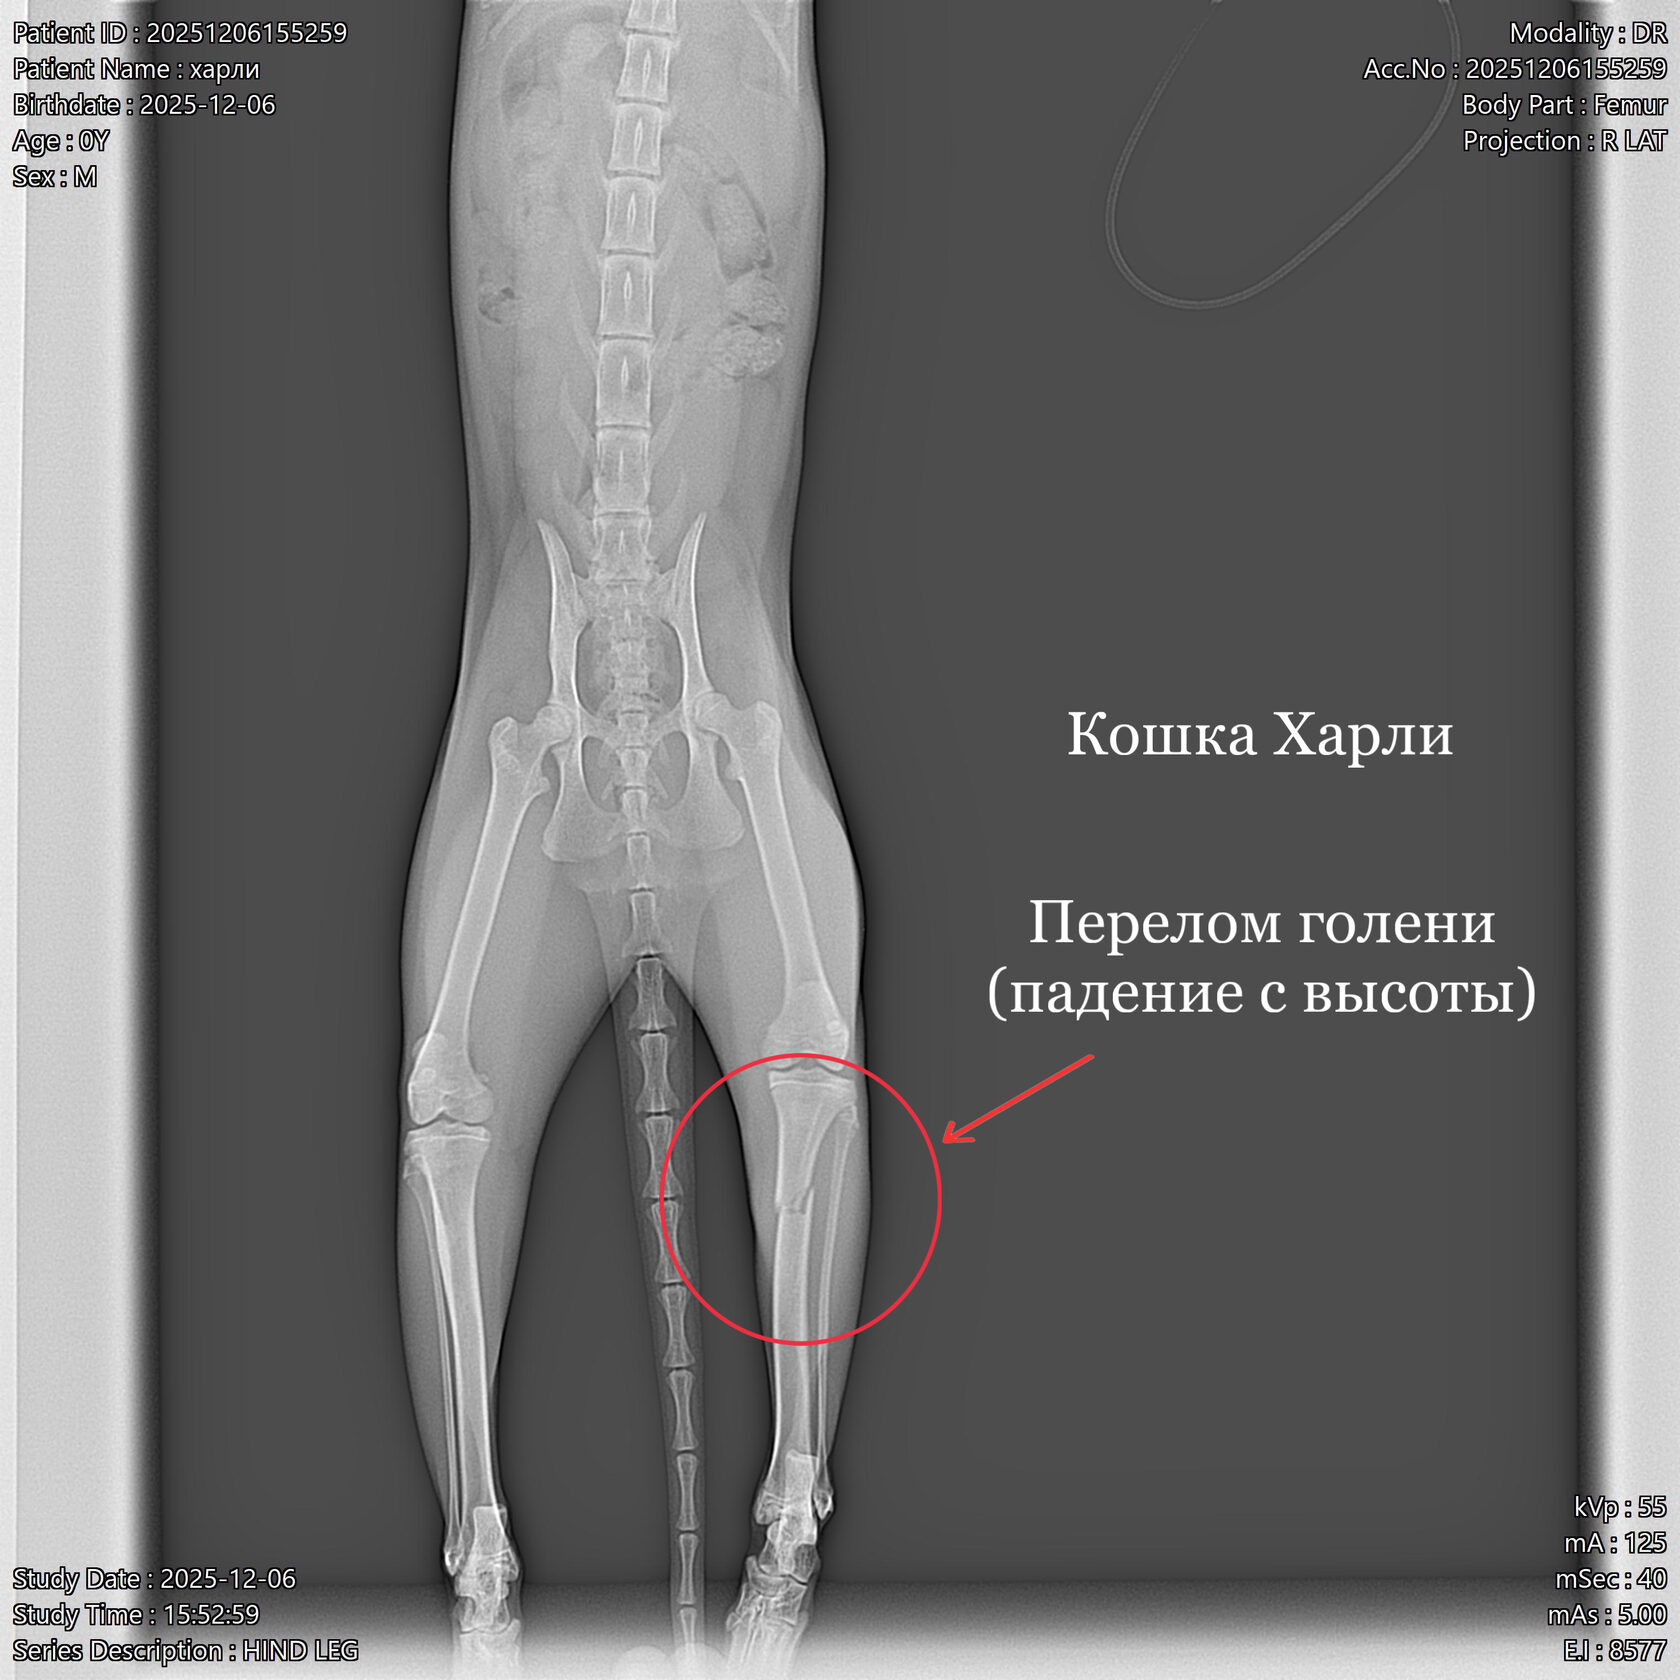

Хоть кошки имеют хорошую мобильность суставов, в отличии от собак, они тоже подвержены переломам конечностей. Такие травмы происходят при падениях с высоты, ущемлениях конечностей. Перелом являются серьезной травмой, требующей немедленной ветеринарной помощи.

Перелом хвоста у кошки может произойти вследствие защемления дверью, окном, складной мебелью либо вследствие неудачного приземления после прыжка с высоты, например, с подоконника.